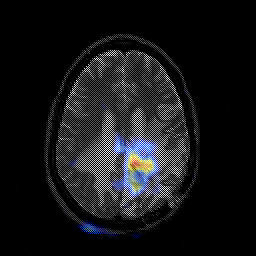

Glioblastoma multiforme overlay -- Slice #35

[Home][Help][Clinical][Tour 1][Tour 2][Tour 3] Slice 35